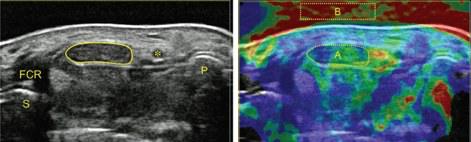

The simultaneous application of structural and functional imaging techniques is described as multiparametric (MP) (Fig. 9). Studies have shown that the MP approach results in greater diagnostic accuracy (Fig. 10).

The use of fusion imaging in uroradiology improves ultrasound lesion-detection rates, shows more reliable size controls at different time points, is an alternative to in-bore biopsies (Fig. 11) and can be used for focal therapy.

• Sonography of carpal tunnel: definition of cut-off values

• Sonographically guided (SG) injections in CTS: sonoelastographic appearance

• SG peripheral nerve injection: sonomorphology

• MR tractography (DTI, ADI) in median nerves of healthy volunteers and CTS patients: comparison with sonography.

The surgical ultrasound section is a leader in the development of ultrasound techniques for the evaluation of peripheral nerves, ultrasound-guided nerve root infiltration and pain therapy. One of the most recent publications illustrates our work.

The axillary nerve (AN) is frequently injured during shoulder trauma and imaging is required to define the site and extent of nerve injury. However, the AN has a rather complex course through several soft tissue compartments of the shoulder and axilla. Detection and sonographic assessment therefore require thorough knowledge of the local topography.

Our investigation aims to define reliable, anatomical landmarks for AN sonography in volunteers and later to validate the proposed sonographic examination protocol in patients. With strict adherence to the proposed examination algorithm, sonography of the AN was feasible in all volunteers and patients. The findings correlated nicely with the gold standard of “surgical exploration” in respect of the severity and topography of neural impairment.

Based on our study results, we propose our algorithm for AN sonography as the first-line imaging tool for the assessment of axillary nerve trauma (PIC).